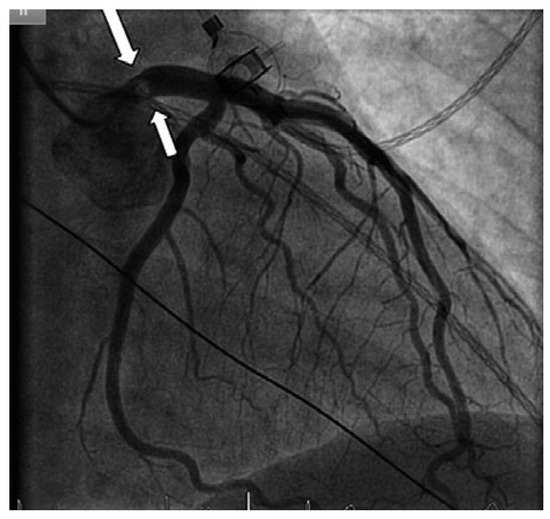

Direct His bundle pacing has recently attracted interest as a more physiological alternative to right ventricular or biventricular stimulation. The advent of new tools has facilitated the implantation procedure. This report relates our initial experi...